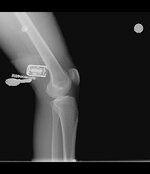

Patella kondromalezi : Sol diz grade 1, sağ diz grade2/3 .

bugün baltalimanındaki spor hekimine gittim canan hanım mr ve röntgen istedi, röntgeni çektirdim mr ıda çektircem sonra gidicem bakalım ama dizler pek güzel durmuyor :)

diz1.jpg diz2.jpg diz3.jpg